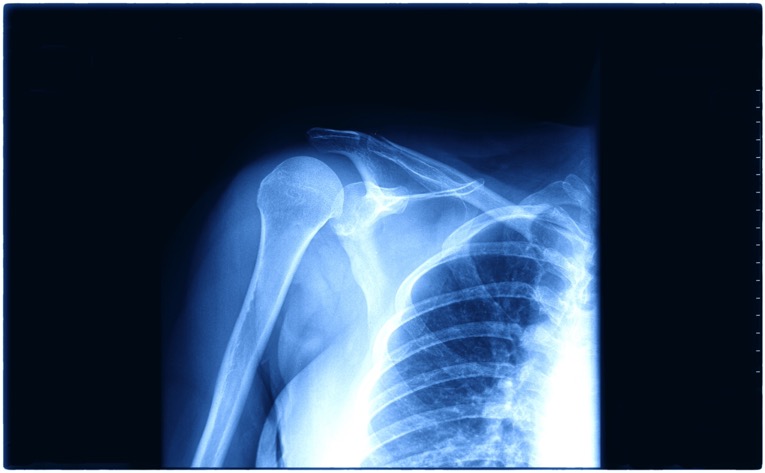

La cirugía de reemplazo de hombro, también conocida como artroplastía de hombro, es un procedimiento que sustituye las superficies dañadas de la articulación por componentes protésicos diseñados para aliviar el dolor y mejorar la movilidad.

Consiste en retirar las partes dañadas del húmero y la glenoides y reemplazarlas con implantes médicos. Existen distintos tipos de prótesis, cuya elección depende del estado del hueso, el cartílago y los tendones.

Antes de indicar una artroplastía de hombro, se realiza exploración física y estudios de imagen como radiografías y resonancia magnética para confirmar el diagnóstico y planear el procedimiento.